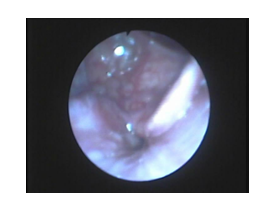

Figure 2 Partial obstruction at the level of soft palate.

Figure 3 Complete latero-lateral collapse at the level of soft palate especially the tonsils.

1. Oropharynx: most patients 75.8% had concentric obstruction while 9.1 % had antero - posterior obstruction and 15.1 % had latero-lateral obstruction.